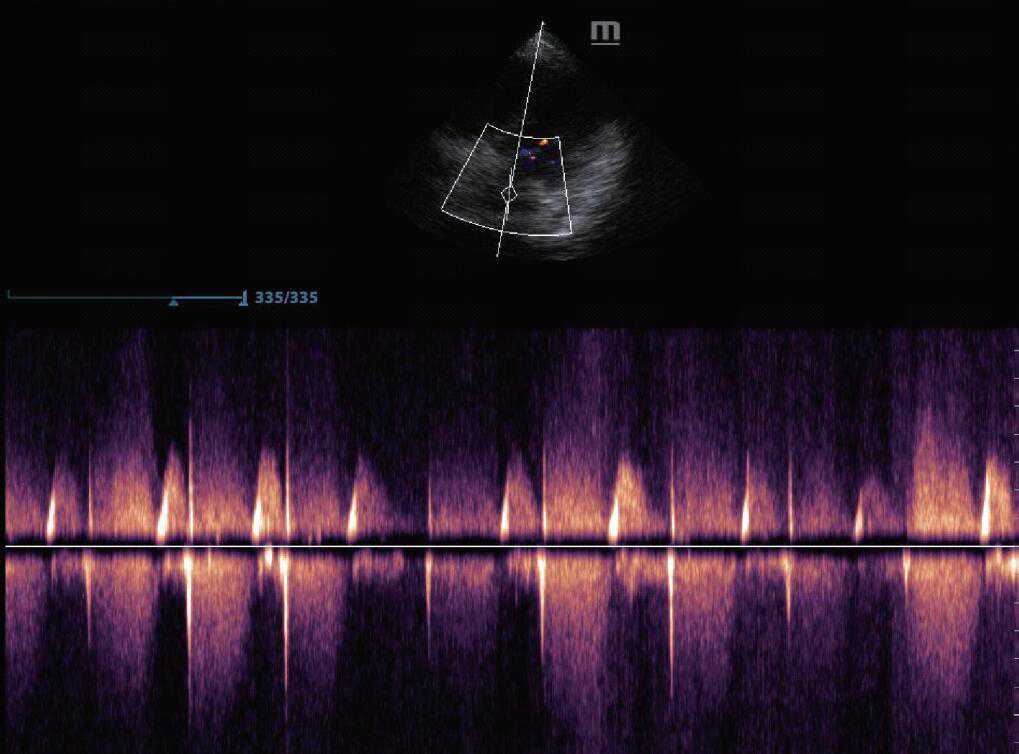

(1)脉冲多普勒(PW):探头间断发射与接收的超声波脉冲,所显示的是声束上某一深度的血流速度、方向和性质。其具有距离选通能力。可定点测定选定区域的瞬时血流频谱,但易受尼奎斯特频率的影响,出现频谱混叠现象,因此不能定量测定高速血流(图4)。

图4脉冲多普勒模式